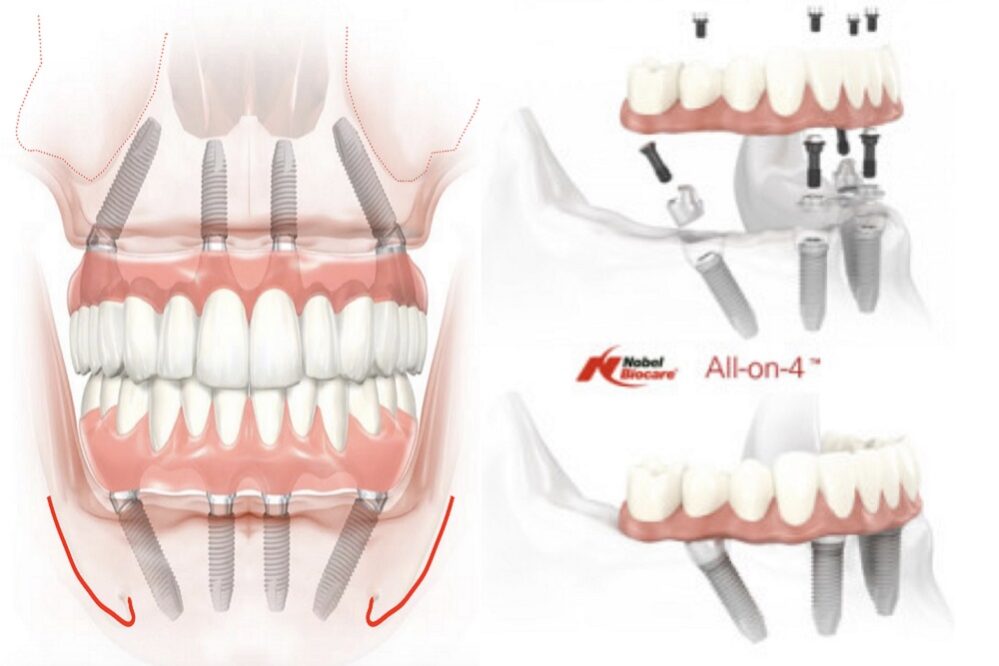

All-on-four therapy concept of the edentulous jaw consists of placing four dental implants and replacing twelve teeth in one jaw. Due to progressive bone loss in lateral regions of the lower and upper jaw or increase (pneumatisation) of maxillary sinus in the upper jaw and proximity of the mandibular nerve in the lower one, we often need big bone augmentations, so that we can ensure adequate bone volume for the integration of implants.

All-on-four therapy treatment enables rehabilitation of all lost teeth without the necessary bone augmentations. What is it about? There is often enough bone volume in the anterior part of the jaw to place the implants. By modifying the technique of an implant bed preparation, lateral implants are placed with inclination, so that the load field is increased, and consequently, we can replace a series of twelve teeth with the placement of only four dental implants.